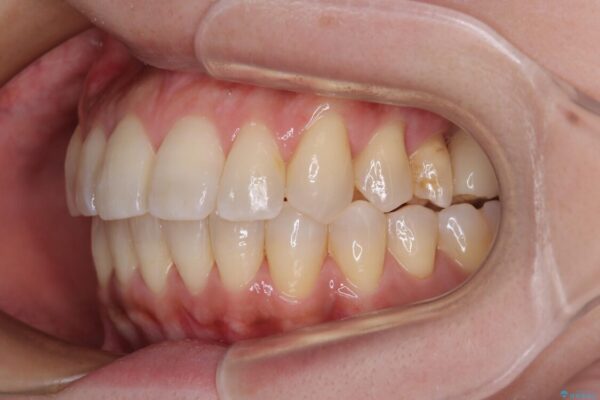

治療後について

歯の傾斜が改善され、インプラントによるクラウンが装着されたことで、物が挟まることもなくなりました。

治療後

• インビザラインによる矯正治療と奥歯のインプラント治療 治療後画像